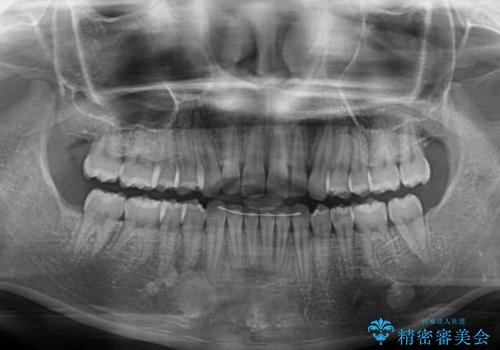

- 口元のデコボコと深い咬み合わせ(ディープバイト)を気にして来院された患者様です。

インビザラインによる上下歯列の拡大と、IPR(歯と歯の間を削る)にるスペースの獲得により、口元のデコボコとディープバイトを改善することとしました。